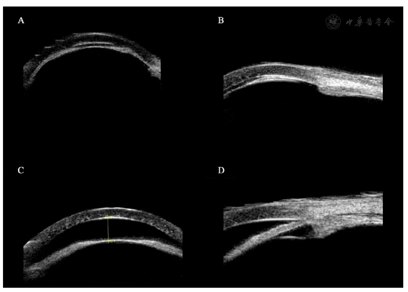

术后3 h,患者右眼眼压降低至32.2 mmHg,前房开始加深(图2A),睫状突前旋转(图2B)。术后第6天,眼压降低至10.3 mmHg,前房深度为1.50 mm,睫状体后旋转(图2C、图2D),予以停用阿托品眼用凝胶及降眼压药物。术后3个月,患者右眼眼压为16.9 mmHg,术后8个月,右眼眼压为16.1 mmHg。在此期间,患者未再使用阿托品眼用凝胶等睫状肌麻痹剂及任何降眼压药物,未见并发症,右眼前房深度逐步加深(术后8个月为1.82 mm),裸眼视力提高到0.3,并保持稳定。

体格检查:生命体征平稳。专科检查:裸眼视力,右眼0.05,左眼0.5;眼压,右眼48.3 mmHg(1 mmHg=0.133 kPa),左眼10.7 mmHg。右眼结膜充血,上方滤过泡扁平,角膜水肿,前房消失,全周虹膜与角膜内皮面接触(图1A),虹膜纹理清,上方虹膜周切口通畅,瞳孔欠圆,直径约3 mm,对光反射消失,晶状体混浊,小瞳下隐约见视乳头界清色淡红,C/D约0.6,黄斑区色素紊乱,全周血管弓外见大量骨细胞样沉着。左眼结膜无充血,上方滤过泡弥散,角膜透明,前房浅,周边前房约1/3 CT,瞳孔圆,直径约3 mm,对光反射存,晶状体混浊,小瞳下隐约见眼底视乳头界清色红,C/D=0.3,黄斑区色素紊乱,全周血管弓外见大量骨细胞样沉着。

辅助检查:眼轴,右眼21.78 mm;左眼21.53 mm。UBM(图1B)检查提示右眼抗青光眼术后,右眼睫状环阻滞。B超:双眼玻璃体轻度混浊、后脱离。